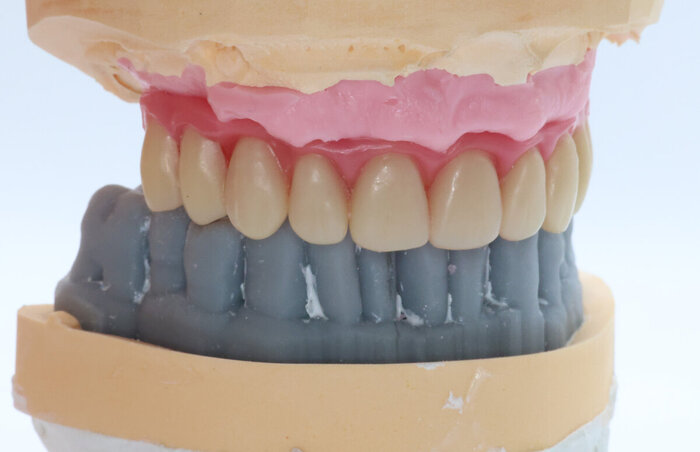

А теперь посмотрим на картину с антагонистами.

Важно - мы не переделывали прикус! А повторили тот, что у пациента уже был, только высоту вернули.

Проверяем попадание в прикус.